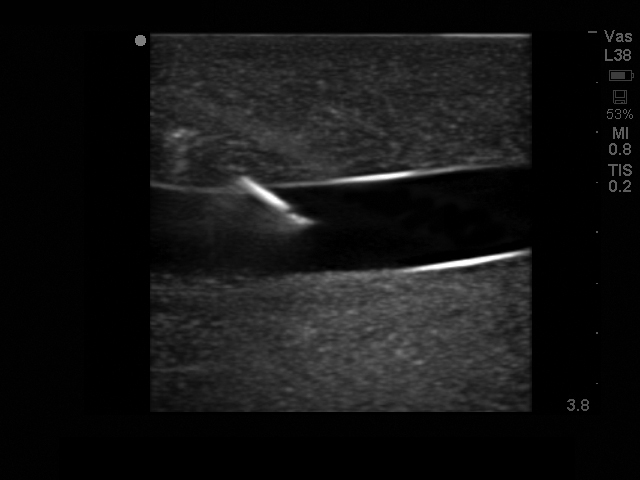

超声引导下颈内中心静脉穿刺术超声训练模块

型号:PC-BP009/PC-BP009.01

模型提供了极佳的真实感,给练习中心静脉置管术提供了最为经济实惠的操作模型